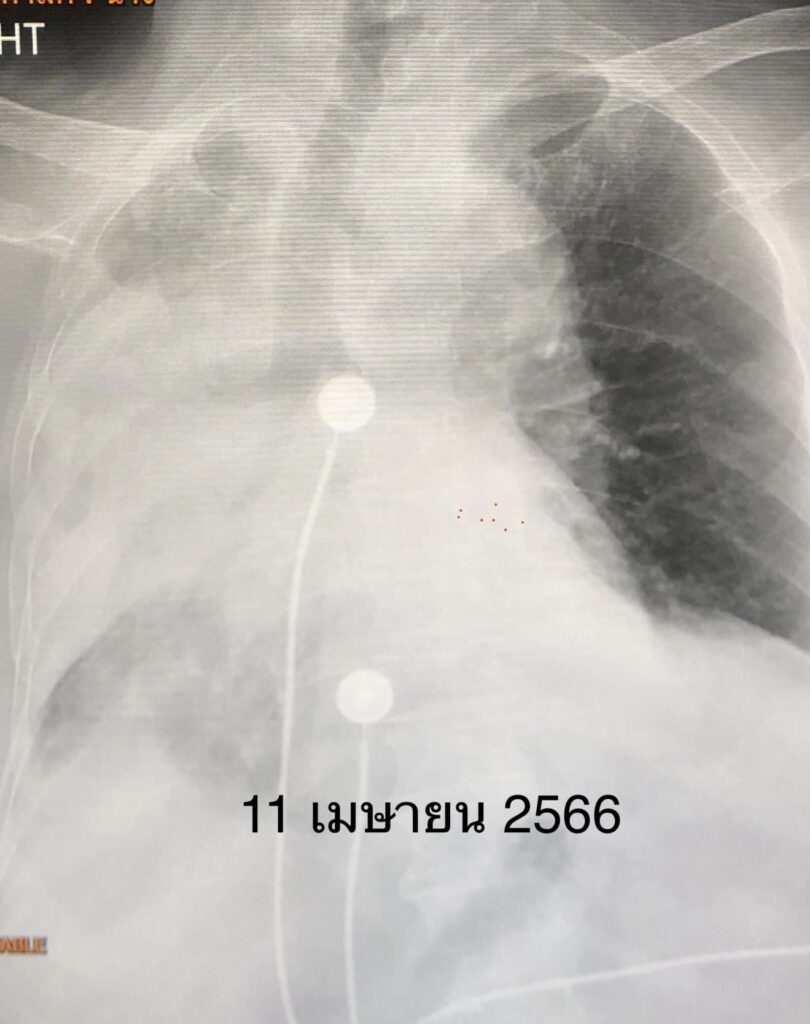

หลังใส่ท่อหายใจดูดเสมหะ เอกซเรย์ปอดดีขึ้น (ดูรูป) ให้ยาปฏิชีวนะร่วมด้วย 7 วันต่อมาคนไข้ดีขึ้น ถอดเครื่องช่วยหายใจได้

นอนรักษาในรพ.รวมทั้งหมด 29 วัน ในที่สุดกลับบ้านได้ เอกซเรย์ปอดดีขึ้น (ดูรูป) คนไข้กลับไปอยู่ในสภาพเดิมก่อนเข้าโรงพยาบาล